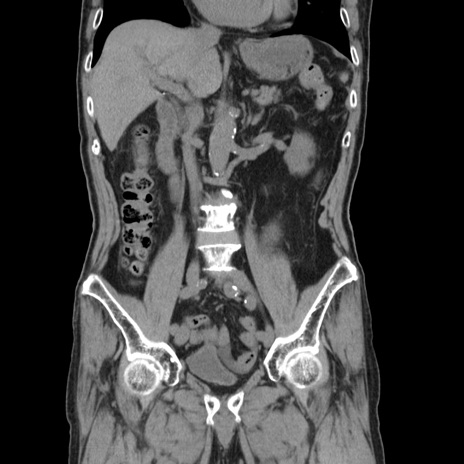

症例24(冠状断像)

【症例】80歳代男性

【主訴】左側腹部痛、嘔吐

【現病歴】本日早朝より左腹部に痛みあり。昼頃嘔吐認めたため、救急要請。

【既往歴】直腸癌(Mile手術)、胆摘

【身体所見】意識清明、BT 35.9℃、BP 221/93mmHg、SpO2 97%(RA) 、腹部:左ストーマ周囲に限局性の腹部膨隆あり。 膨隆部自発痛・圧痛あり・軟。

【データ】WBC 7700、CRP 0.09